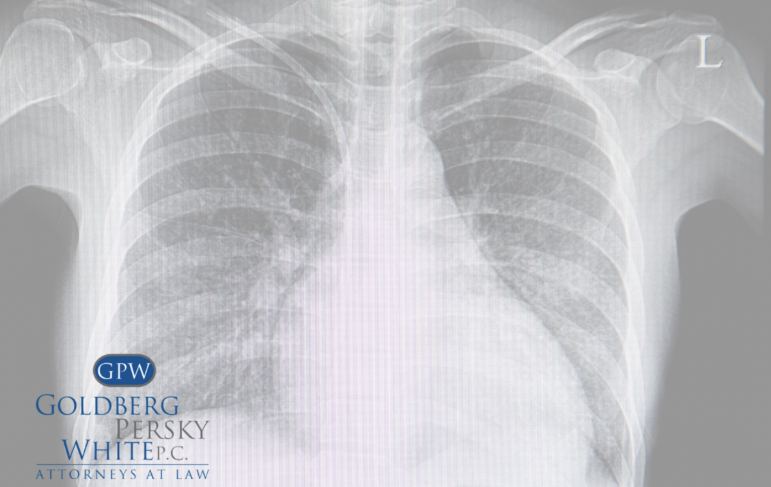

When asbestos is inhaled or ingested, the fibers travel into the small airways and irritate the lung lining and pleura. Since the body cannot eject the asbestos fibers, irritation results in inflammation and damage that eventually leads to abnormal cancer cells. The abnormal cell growth becomes a tumor while fluid accumulates in the pleura space.

Mesothelioma is cancer that begins in cells in the linings of certain parts of the body called the mesothelium. The mesothelium is the lining that helps protect bodily organs by making a unique lubricating fluid that permits organs to slide against each other. Mesothelioma cancer can effect the lungs, abdomen, heart, and testicles. Pleural mesothelioma, which effects the lungs is the most common type of mesothelioma.

Pleural mesothelioma is the most frequently diagnosed type of mesothelioma.